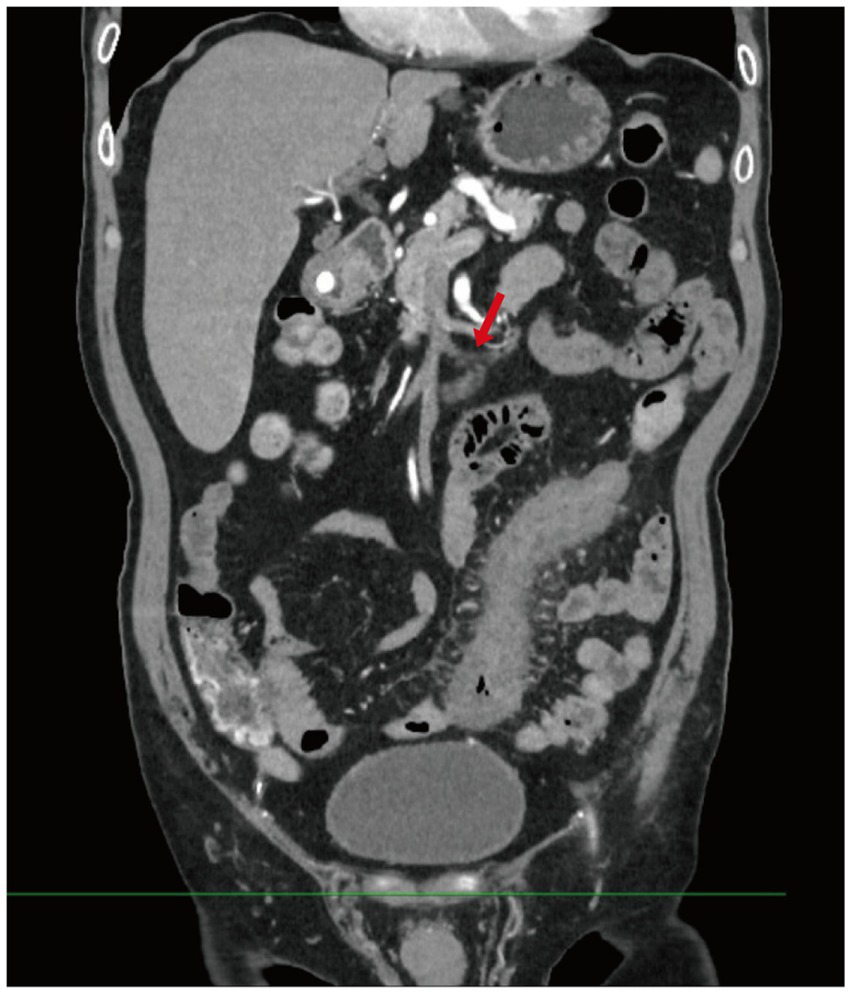

Contrast-enhanced abdominal CT revealed significant bowel wall edema distal to the previous anastomosis site, suggestive of ischemia (Figure 2). Given the clinical course and inconclusive findings from conservative management, the surgical team proceeded with exploratory laparotomy. The patient underwent a redo left-sided colectomy with resection of the prior anastomosis and adhesiolysis, followed by reconstruction with a new colorectal anastomosis. Intraoperative findings included dark purple discoloration and mesenteric ischemia involving the bowel from 10 cm above the anal verge to the mid-sigmoid colon, without evidence of arterial occlusion or torsion. Histopathological examination revealed extensive acute and chronic inflammation, edema, and ulceration of the bowel wall. Notably, marked smooth muscle proliferation within the intima of mesenteric veins, leading to luminal narrowing or occlusion, was observed from mucosa to serosa. In contrast, the mesenteric arteries in the submucosa and subserosa were structurally preserved, with intact elastic laminae and no evidence of inflammation, thrombosis, or intimal hyperplasia. Representative histopathological images are shown in Figure 3, including a low-power mucosal view with ischemic ulceration (panel A), high-power elastin stain differentiating uninvolved arteries from affected veins (panel B), high-power H&E showing concentric venous intimal hyperplasia (panel C), and corresponding smooth muscle actin (SMA) immunohistochemistry confirming proliferation of intimal smooth muscle cells (panel D). Elastic fiber staining and immunohistochemistry for SMA confirmed the diagnosis of idiopathic myointimal hyperplasia of mesenteric veins (Figure 4). No evidence of malignancy was found in the resected bowel or in 22 reactive mesenteric lymph nodes. Postoperatively, the patient’s symptoms improved rapidly. Bloody diarrhea resolved by postoperative day 3, liquid diet was resumed on day 7, and serum electrolytes and D-dimer levels normalized by day 14. He was subsequently discharged in stable condition.

Figure 2

Contrast-enhanced abdominal CT. This image shows diffuse bowel wall thickening and mucosal enhancement involving the descending and sigmoid colon, with dilation of several adjacent bowel loops. Multiple engorged and tortuous mesenteric vessels are visualized, along with mild stranding of the surrounding mesenteric fat (Red arrow indicates tortuous mesenteric veins).